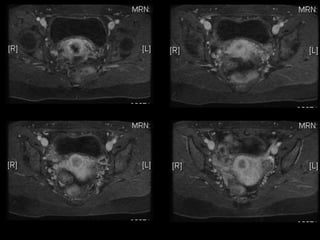

Dr. Hedvig Hricak

HISTORY

•   42 yo female

•   Recent immigrant from China

•   C/O postcoital and intermenstrual bleeding

•   Abnormal GYN exam

•   Abnormal biopsy

•   Further imaging performed

• What is the diagnosis?

• Staging?